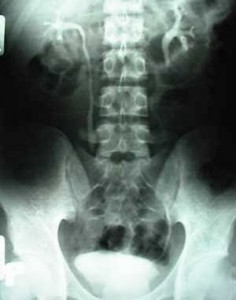

Bệnh vôi hóa cột sống là một bệnh thường gặp ở người lớn tuổi. Bệnh xảy ra là do quá trình cơ thể sửa chữa các khớp bị tổn thương nhưng lại gây nên việc cái gai xuất hiện. Các gai xuất hiện ở các cạnh và phía trước cột sống. Thường khi mới bị bệnh, người bệnh rất khó nhận ra mình bị gai vì triệu chứng đau cũng có thể xuất hiện ở các bệnh khác như viêm khớp hoặc đau khớp. Bệnh thường được phát hiện thông qia việc chụp X-quang. Chính vì vậy khi bị bệnh nhân có triệu chứng đau thì tốt nhất nên đi tới bệnh viện để được khám và chuẩn đoán để có phương pháp điều trị bệnh hợp lý.

Vôi hóa cột sống dễ phát hiện khi chụp X- quang